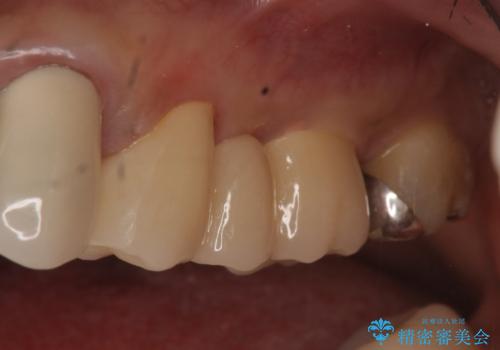

古いブリッジを除去後、オールセラミッククラウンによる補綴を行いました。

今回用いたオールセラミッククラウンは、ジルコニアフレームという白い素材の上にセラミックを盛っているため審美性が非常に高いのが特徴です。

またジルコニアは人工ダイヤモンドの材料にも使われているほど高い強度を持っており、そのためオールセラミッククラウンは審美性だけでなく、奥歯やブリッジの補綴も可能とするクラウンです。